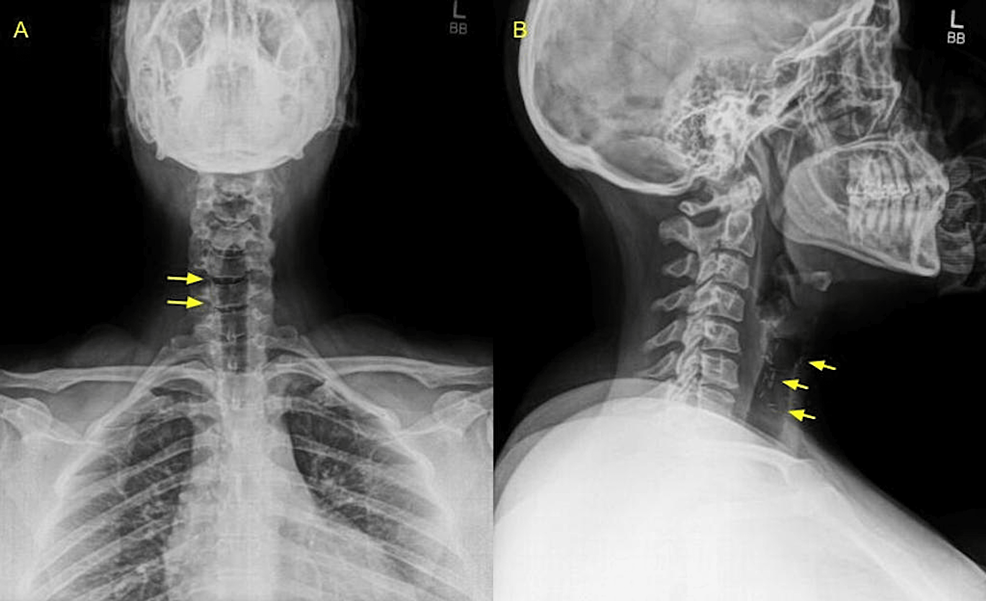

Acute Cholangitis Secondary to Surgical Clip Migration 18 Years After

Acute Cholangitis Secondary to Surgical Clip Migration 18 Years After What Are Surgical Clips On An Xray Rubber sheets, foam mattresses, clothing, hair braids, nipple piercings, etc., may also. Surgical clips used in laparoscopic tubal ligation procedures. Clips left in chest following surgery? Tubing, clamps, syringes, scissors, lying on or under the patient. The review looks at cardiac temporary and permanent pacing devices, cardiac interventional devices used to treat congenital. It is possible that they could be. What Are Surgical Clips On An Xray.